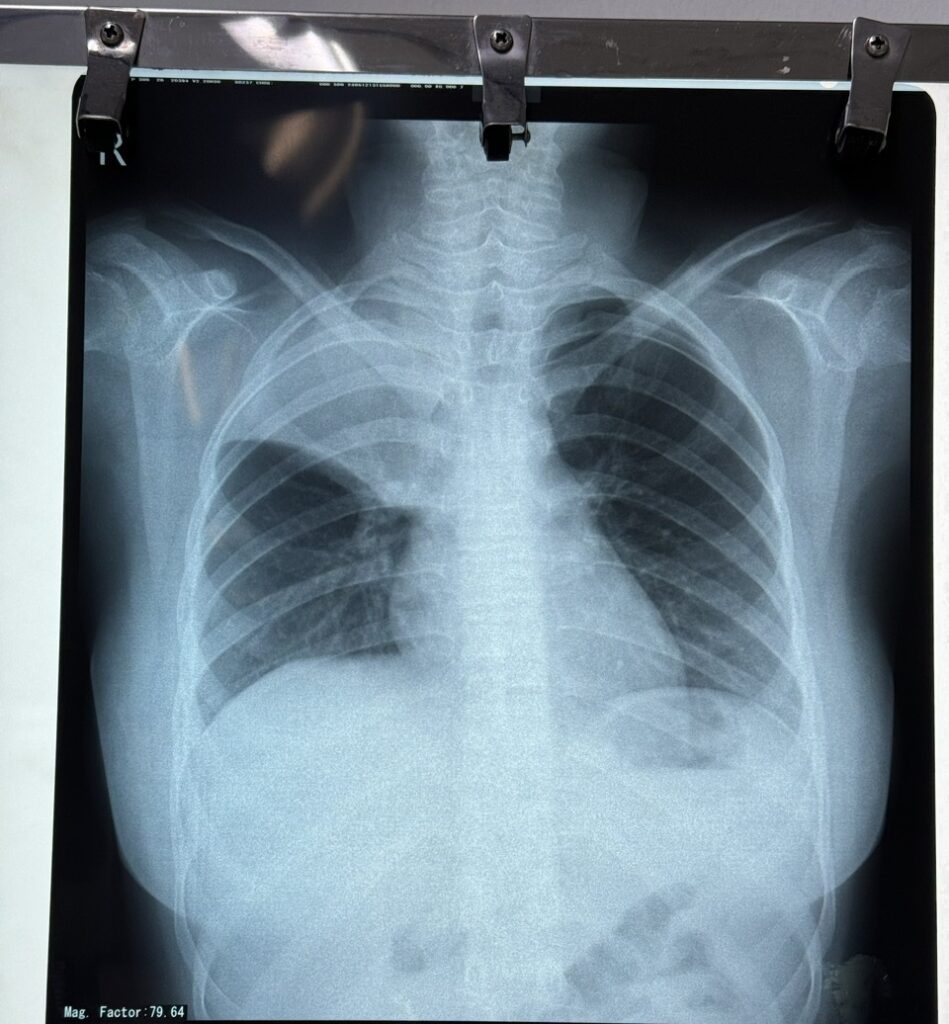

Các bác sĩ Bệnh viện Hoàn Mỹ Cửu Long vừa phẫu thuật nội soi lồng ngực cắt bỏ khối u nang trung thất khổng lồ chèn ép tim phổi. Bệnh nhân là chị D.T.D.M (30 tuổi, địa chỉ tại huyện Long Phú, tỉnh Sóc Trăng) nhập Bệnh viện Hoàn Mỹ Cửu Long vì ho khan, […]